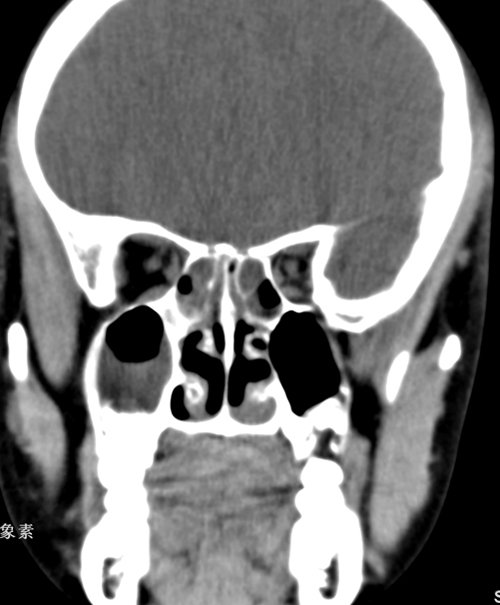

标题: PED0731:女,10,鼻塞半月伴头疼,双下鼻甲肥大 [打印本页]

标题: PED0731:女,10,鼻塞半月伴头疼,双下鼻甲肥大

全组副鼻窦炎症。

副鼻窦炎并鼻甲肥大

支持全组副鼻窦炎症(左侧上颌窦粘膜下囊肿)。

全组副鼻窦炎症。右侧上颌窦囊肿。

所见前组鼻窦炎,蝶窦位于颅底,不属显示范围。